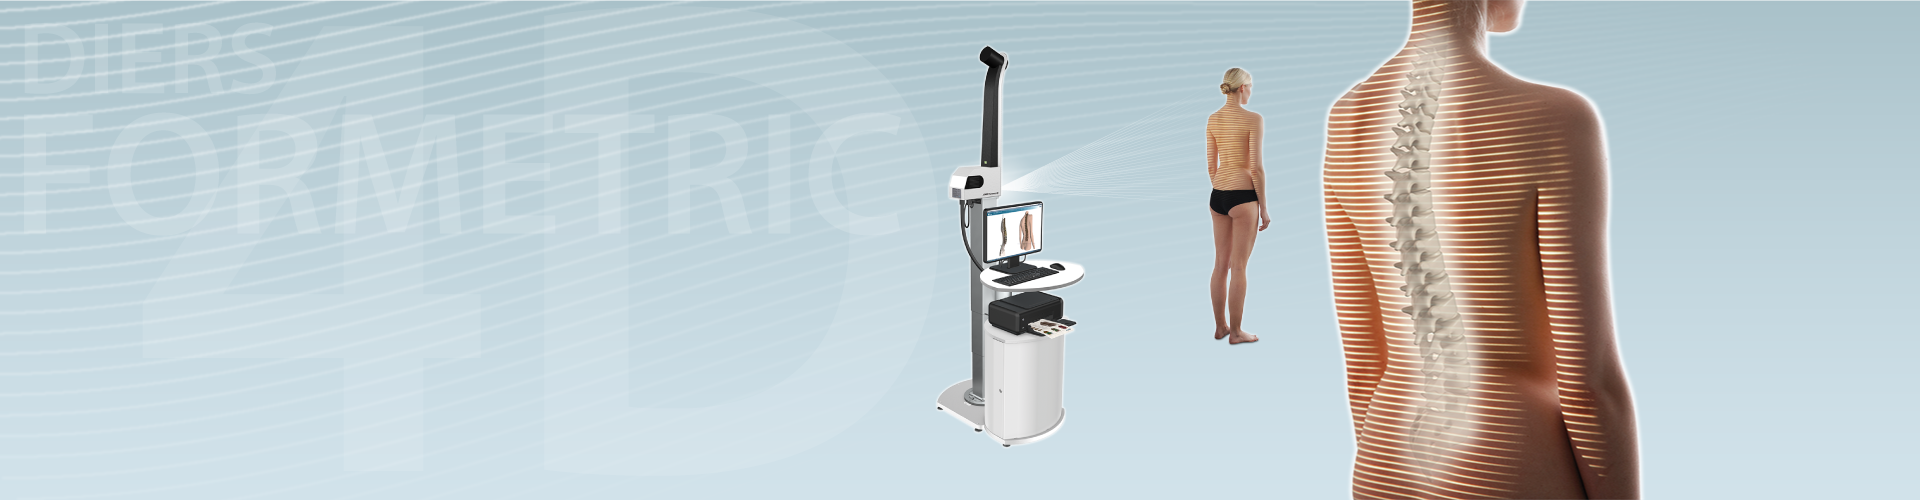

Оптическая диагностика позвоночника Diers: изображения и технологии

Раздел: Мир в картинках